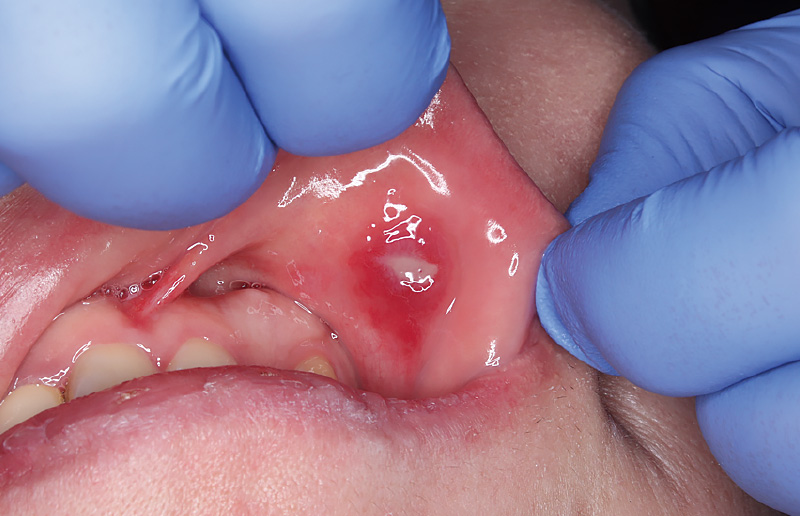

![[写真] 下唇の口内炎](/academic/dentalmagazine/wp-content/uploads/sites/2/2026/04//196-8_photo03.jpg)

図3 下唇の口内炎 -